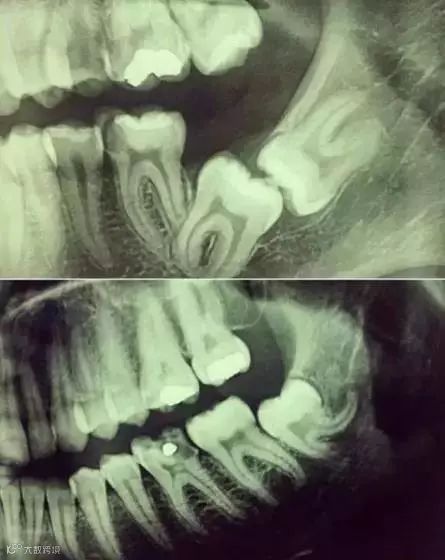

先放几张图,让你们涨涨姿势,不拍片根本不知道你的牙齿长得会有多奇葩!

●牙齿本身:生长方向,牙根数目,牙根是否弯曲,膨大等。

●与重要解剖结构的位置关系:如上颌磨牙与上颌窦的关系;下颌磨牙与下颌神经管的关系;儿童在混合牙列期恒牙与乳牙胚的关系等。可以减少拔牙的风险。

●预知其他病变:如颌骨内有无埋伏牙,多生牙,囊肿等。